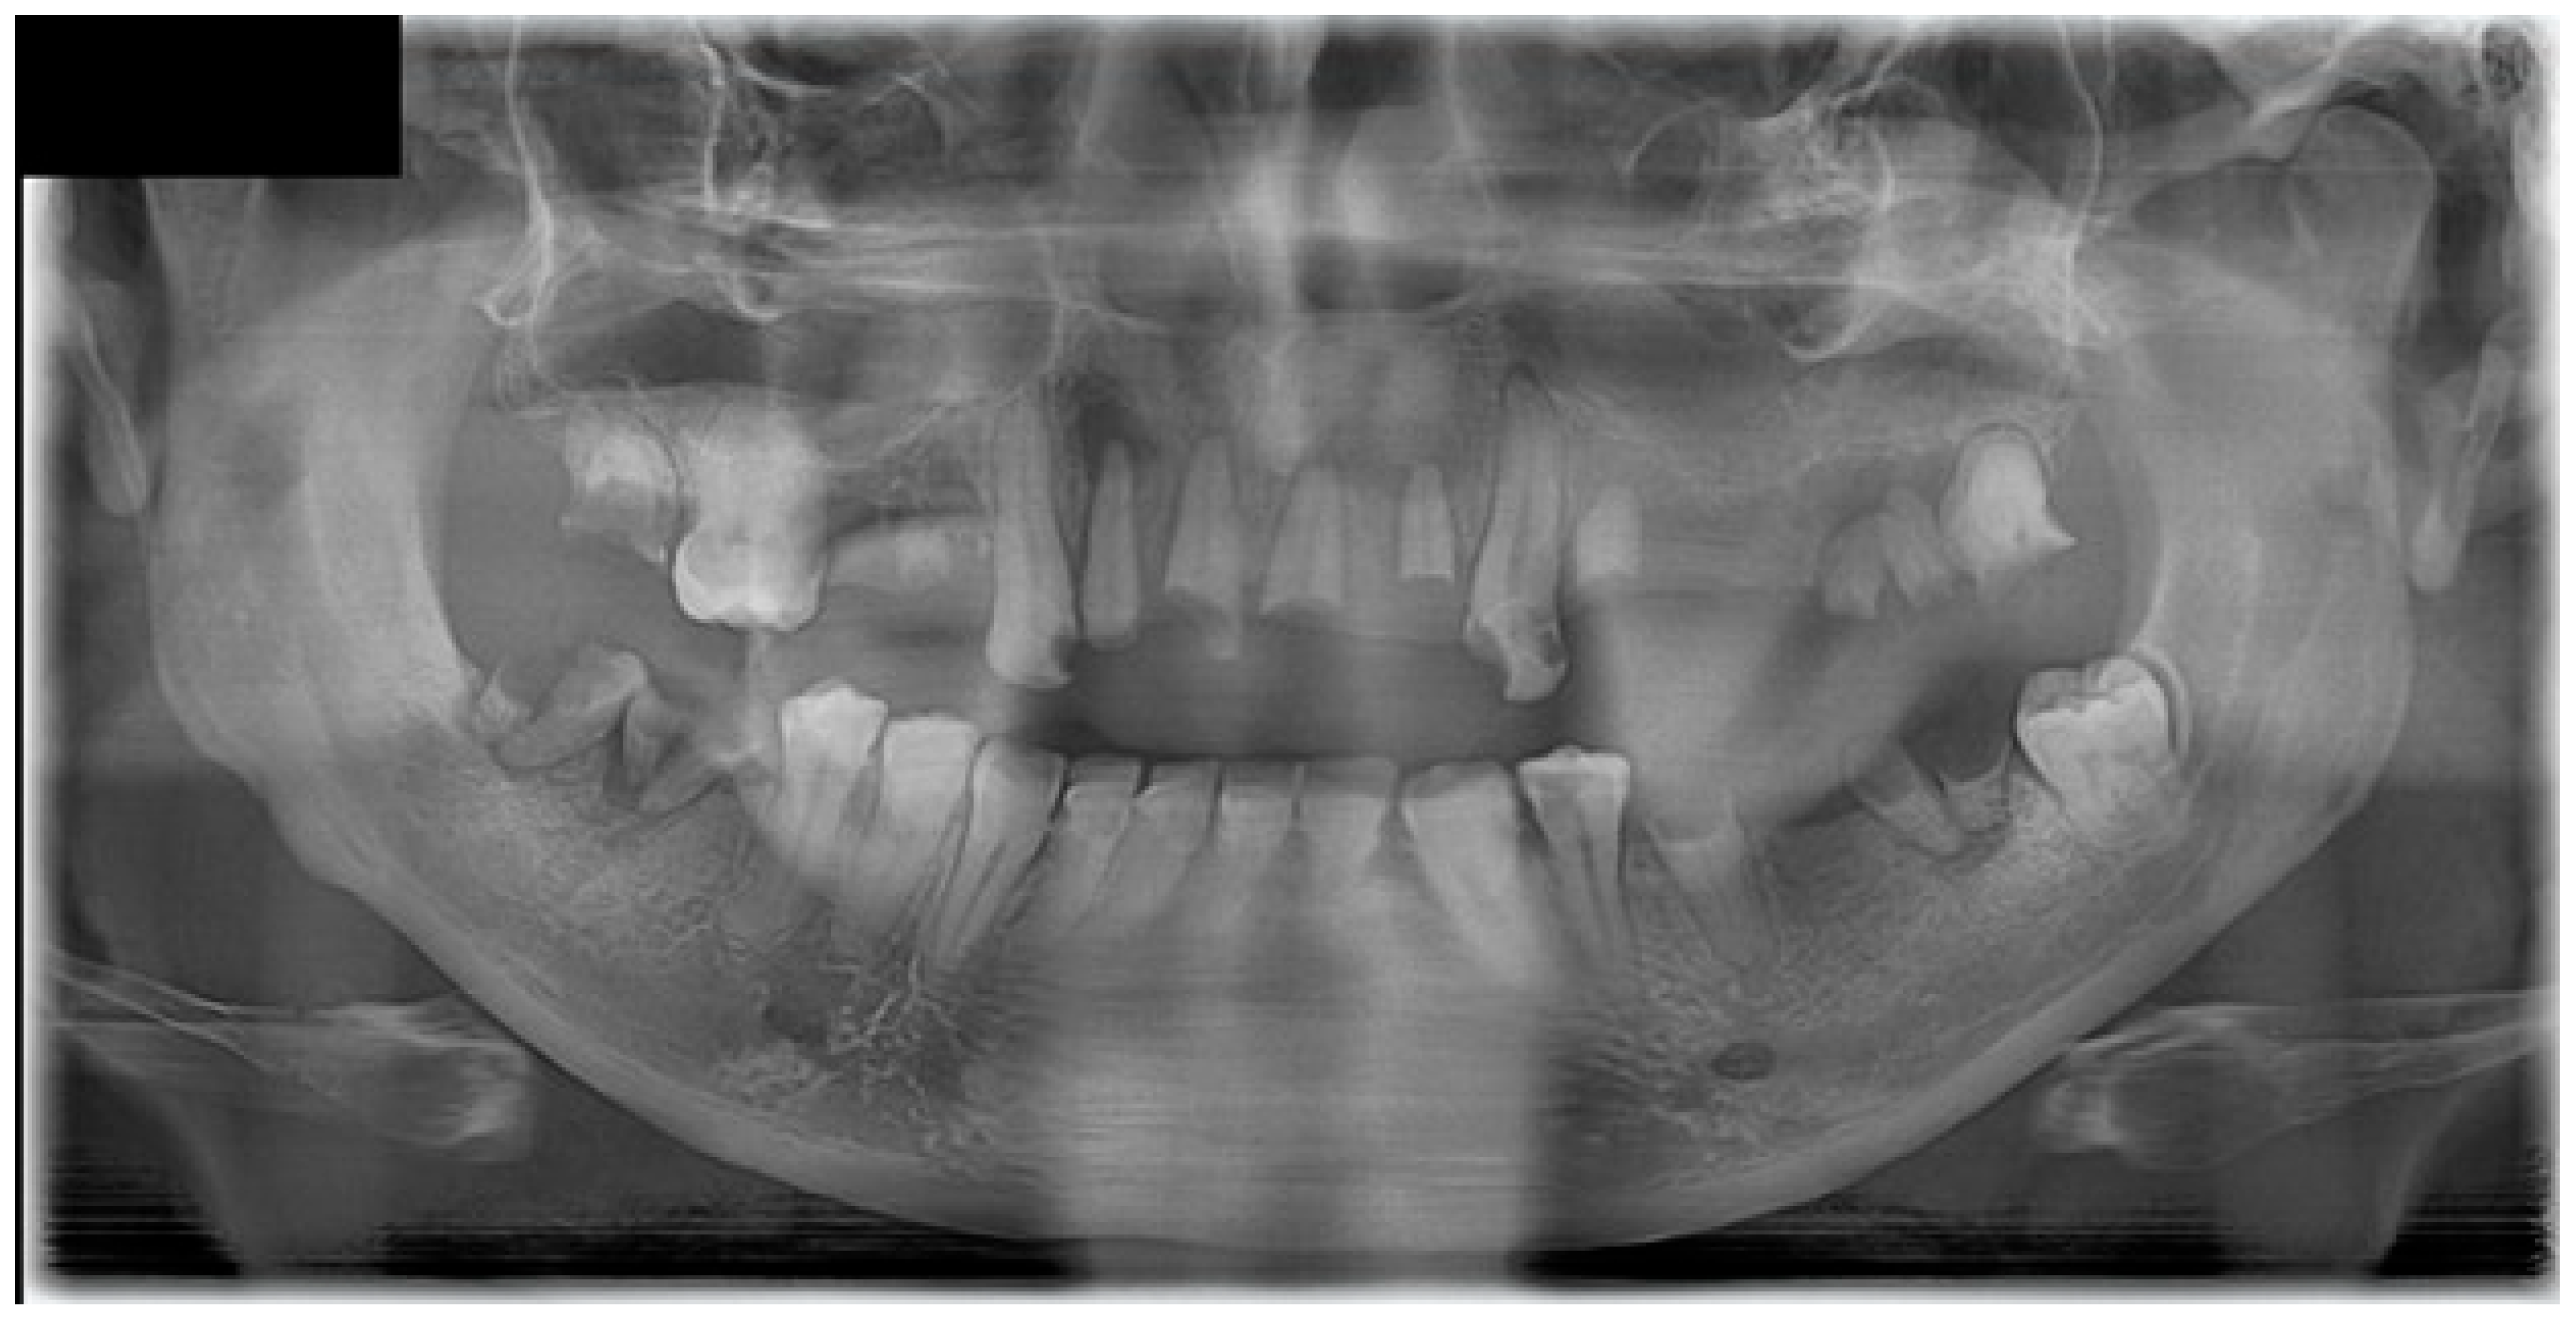

Following a minor facial trauma, the patient developed nonspecific symptoms, including left midfacial discomfort, subjective nasal obstruction in the absence of sinonasal involvement, and dull facial pain. At the time of his first presentation to our clinic, the oral mucosa already showed advanced pathological changes. Physical and radiological examinations did not reveal traumatic injuries or findings that could adequately explain the severity of the clinical presentation (Figure 1 and Figure 2).

Intraoral examination at initial evaluation revealed an ulcerative, bleeding palatal lesion covered by pseudomembranous exudate, accompanied by surrounding inflammation. Additional findings included multiple root remnants, extensive carious lesions, periostitis, and severe dental neglect (Figure 1). Despite targeted ambulatory antibiotic therapy, antifungal treatment (fluconazole 100 mg twice daily), and local dental interventions, the lesion failed to regress and demonstrated further progression, with increasing tissue destruction involving the palate, left maxillary process, and adjacent gingival tissues. Periodontal swelling and pathological mobility of the maxillary teeth were also observed.

Figure 2. Panoramic radiograph (dental orthopantomogram, DOP) demonstrating extensive dental pathology and maxillary involvement. The image shows multiple residual roots, advanced carious destruction, generalized periodontal bone loss, and irregular osteolytic changes in the left maxillary alveolar process, corresponding to the clinically affected region. These findings initially supported an odontogenic and inflammatory etiology but did not fully explain the progressive, destructive soft tissue lesion.